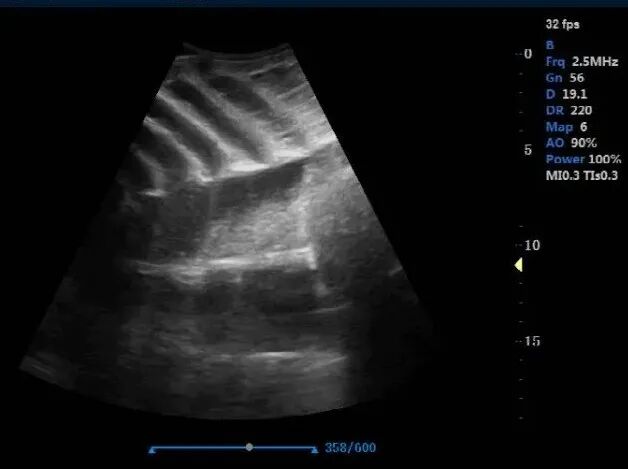

5. Shellfish ultrasound / bivalve ultrasound Case

Objective

- Measure heart rate changes in oysters and scallops under different water temperature conditions, to support aquaculture research and provide practical guidance for farmers.

System

- Dawei L5-VET Laptop Veterinary Color Doppler Ultrasound

- Probe: High-frequency linear transducer (for better superficial-detail imaging)

How it’s used

- Researchers perform ultrasound scanning and record heart rate signals at different temperature settings, then compare trends across groups.

Value

- Converts biological signals into quantifiable data, helping develop science-based temperature management recommendations for shellfish farming.